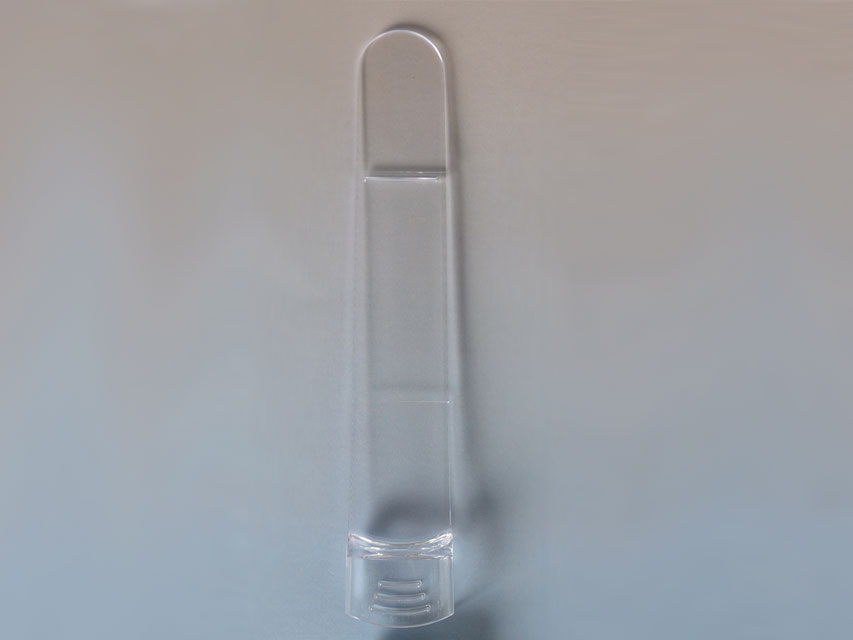

Abbassalingua

Dispositivi monouso progettati per facilitare l’esame del cavo orale e della gola, garantendo igiene e sicurezza durante le visite mediche.

All’interno sono disponibili abbassalingua utilizzati per mantenere abbassata la lingua durante le ispezioni cliniche, permettendo una visualizzazione chiara e accurata delle vie aeree superiori.

Tutti i prodotti sono selezionati per qualità, sicurezza e conformità alle normative, ideali per ambulatori, studi medici, strutture sanitarie e pronto soccorso.

Abbassalingua

Dispositivi monouso progettati per facilitare l’esame del cavo orale e della gola, garantendo igiene e sicurezza durante le visite mediche.

All’interno sono disponibili abbassalingua utilizzati per mantenere abbassata la lingua durante le ispezioni cliniche, permettendo una visualizzazione chiara e accurata delle vie aeree superiori.

Tutti i prodotti sono selezionati per qualità, sicurezza e conformità alle normative, ideali per ambulatori, studi medici, strutture sanitarie e pronto soccorso.